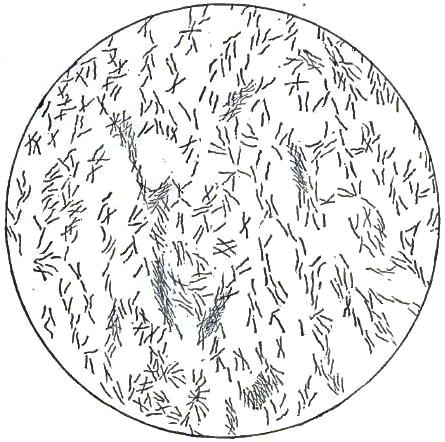

3. BACILLUS MALARIÆ

7. BACILLI FROM SWAMP-MUD